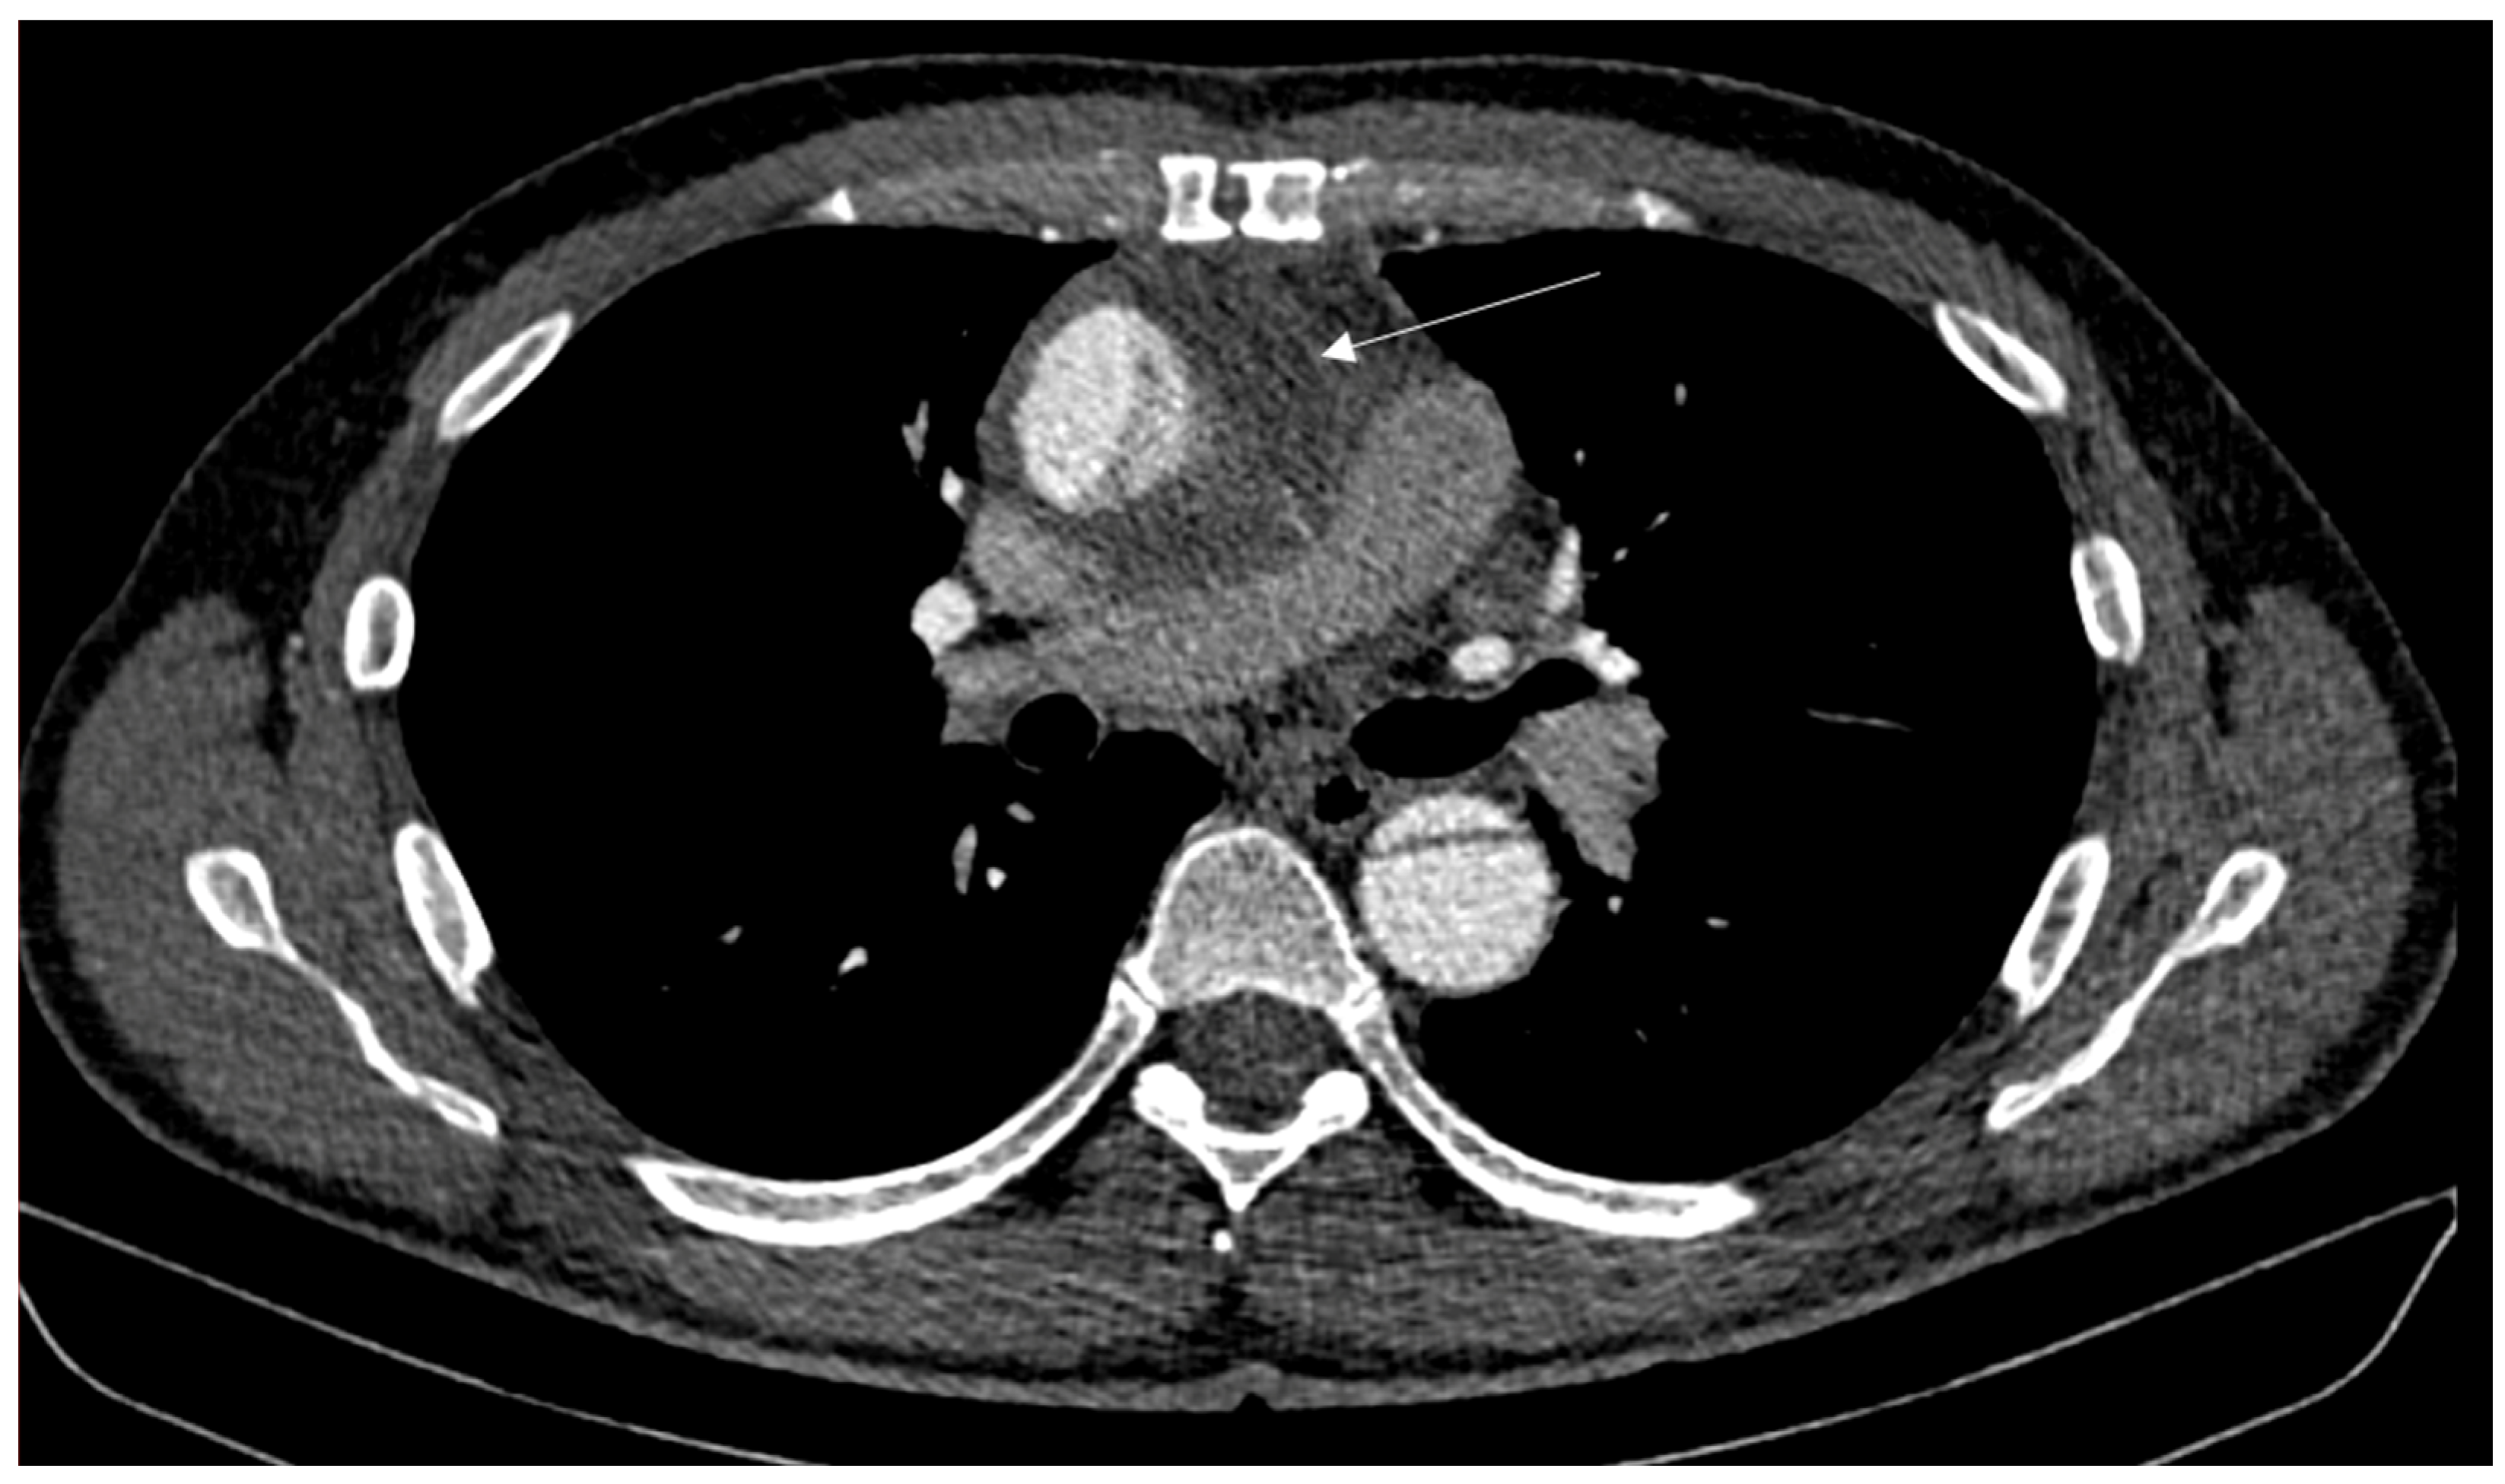

2. Case Report